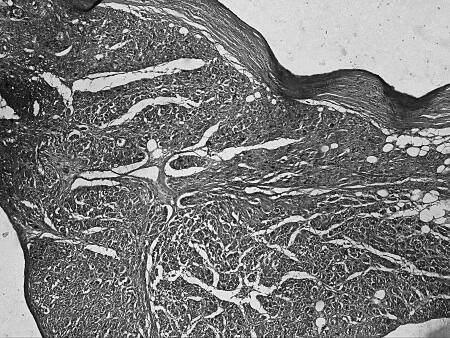

Что же общего среди всех этих состояний и что определяет их патогенетическую взаимосвязь с ФП? Очевиден механизм нарушения электрических процессов в результате ремоделирования миокарда. Данные патологоанатомических исследований подтверждают это. Так, при гистологическом исследовании ткани предсердий умерших пациентов с ФП часто выявлялись следующие изменения (см. рис. 5):

липоматоз, склероз и гиалиноз стенок артерий (см. рис. 5 д).

д)

Рисунок 5.Гистологические изменения предсердий при ФП